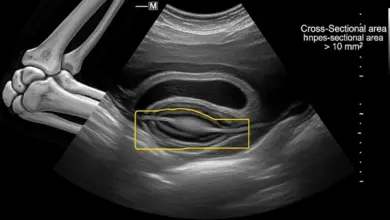

• Ultrassonografia: identifica sinovite espessada e derrame, útil para guiar punções.